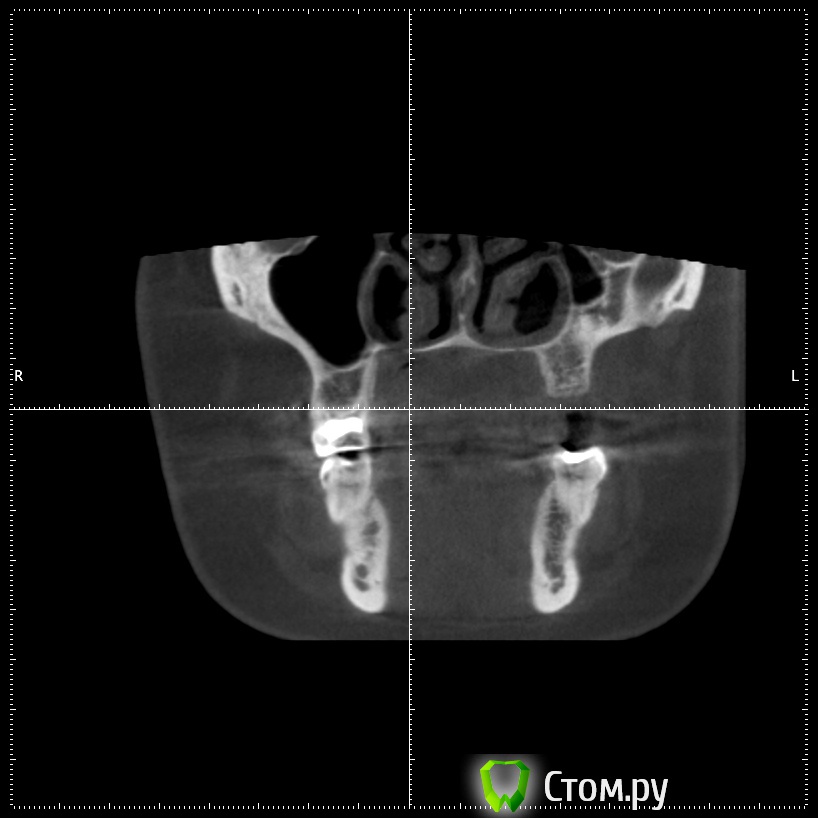

stommm Опубликовано 17 сентября, 2014 Поделиться Опубликовано 17 сентября, 2014 Всем доброго времени суток) Ко мне обратилась пациентка с жалобами на отсутствие зубов во втором сегменте. Сделала кт. Честно говоря такого кт я еще не видел.Что это, господа, вариант нормы или признак патологии? Встречалось ли подобное в вашей практике? Планирую нарастить по ширине и имплантировать, без синуса. Ссылка на комментарий

Bier Опубликовано 18 сентября, 2014 Поделиться Опубликовано 18 сентября, 2014 тут просто пазуха заросла костью, природа сделала синуслифтинг )) 2 Ссылка на комментарий

stommm Опубликовано 18 сентября, 2014 Автор Поделиться Опубликовано 18 сентября, 2014 По данным литературы, в 7-10% случаев может наблюдаться асиметрия пазух (пневматизированная/склерозированная)Я думаю здесь не просто одна пазуха более пневматизированная чем иная. Полость носа тоже кажется довольно несимметричной. тут просто пазуха заросла костью, природа сделала синуслифтинг ))А то что ширина самих пазух отличается сильно, это нормально? Ссылка на комментарий

Alexey Doc Опубликовано 18 сентября, 2014 Поделиться Опубликовано 18 сентября, 2014 Гипоплазия левой гайморовой пазухи. У самого было 2-е похожих пациентов 2 Ссылка на комментарий

dr-krasnov Опубликовано 6 октября, 2014 Поделиться Опубликовано 6 октября, 2014 Гипоплазия левой гайморовой пазухи. У самого было 2-е похожих пациентов Верный ответ. 1 Ссылка на комментарий